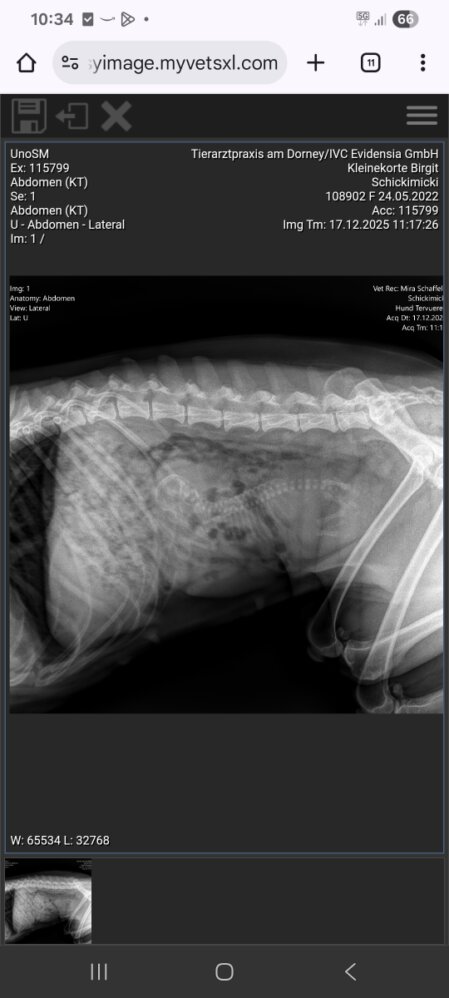

Heute ist der 59. Tag

waren gestern mit Chikimiki zum röntgen,

es bleibt bei Eine oder Einem.